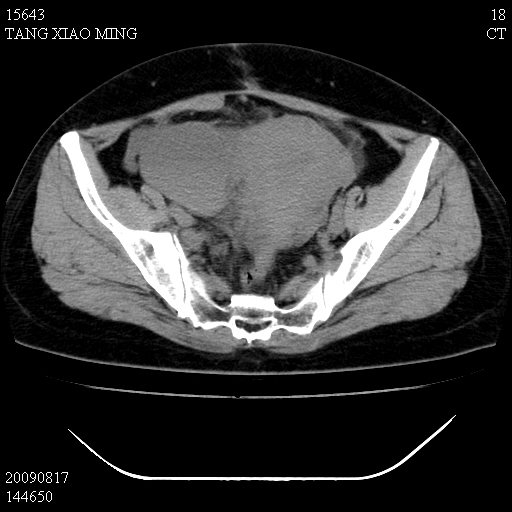

标题: CT21692:盆腔病变

女,33岁,右下腹痛2年余,既往宫外孕病史,如在我院手术,结果下周公布,

可能的诊断。1子宫内膜异位【子宫腺肌症并右卵巢巧克力囊肿】;2 右卵巢囊腺瘤。子宫肌瘤

1)考虑卵巢巧克力囊肿,不排除卵巢囊腺瘤。2)子宫肌瘤可能。

卵巢囊腺瘤,子宫肌瘤,直肠壁厚,不除外占位.